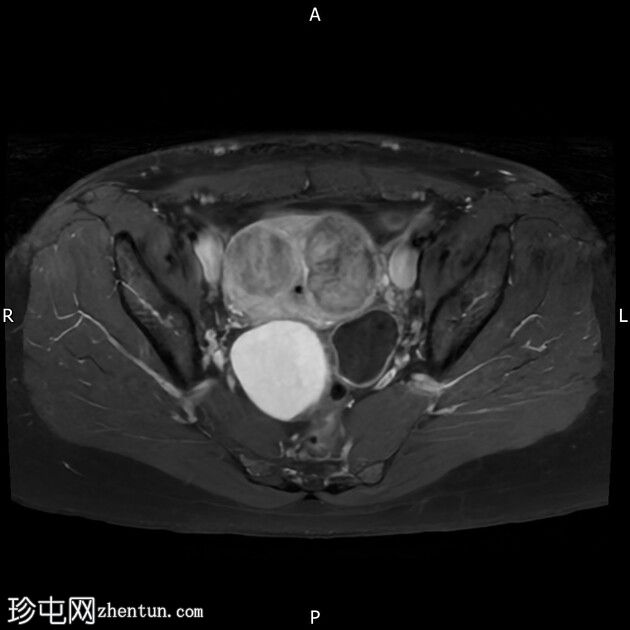

冠状位

T2加权像

右侧卵巢囊肿,T2加权像呈低信号,T1脂肪抑制像呈高信号,大小为6 x 5.2 cm,符合子宫内膜异位囊肿的影像学表现。

左侧卵巢囊肿,T2加权像呈低信号,T1脂肪抑制像呈高信号,符合子宫内膜异位囊肿的影像学表现。

双侧卵巢粘连于后道格拉斯窝,呈“接吻卵巢征”。

多发性子宫肌瘤。宫内放置宫内节育器。